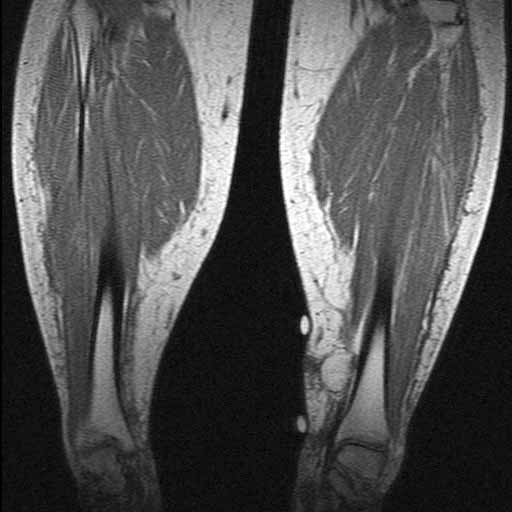

MRI: There is an oval mass with fat density in the left ankle. The mass is very well demarcated from the surrounding tissue without evidence of invasion into the surrounding tissue.

MRI